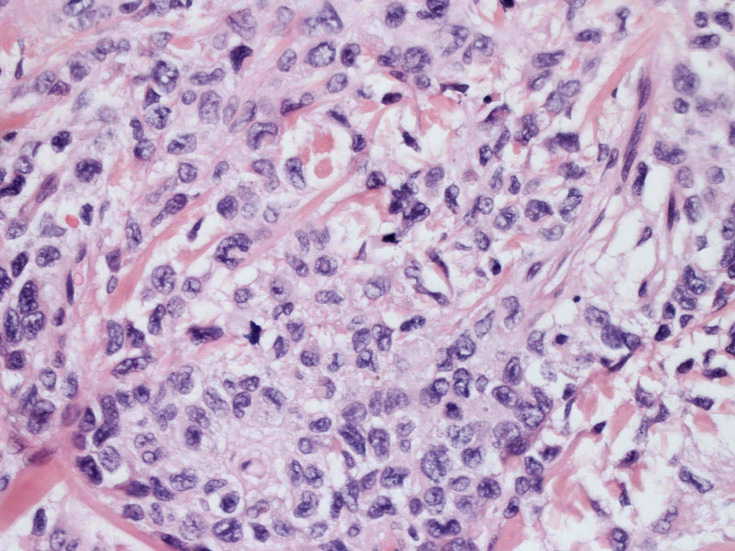

LCSの病理組織所見

Langerhans cell histiocytosisの高悪性度 variantで明らかな悪性像を示すLangerhans cellの腫瘍性増殖と定義される(WHO, 2008)

大型細胞の増殖よりなる腫瘍。縦溝,しわ,切れ込みのある核をもった大型細胞も出現する。クロマチンは顆粒状で核小体も明瞭である。核分裂は >50/10hpfと多い。eosinophilsは少ない。壊死が多発することがある。未分化ないし低分化な細胞像, 組織所見のため鑑別診断は多岐にわたり、的確な免疫染色を行う必要がある。

皮膚に異型細胞の浸潤がみられる。異型細胞は表皮内に浸潤するほか、表皮真皮境界部, 真皮, 皮下脂肪組織にもびまん, 結節様の浸潤所見を示す。血管周囲に浸潤、集蔟する所見も多く見られる。 増殖浸潤細胞の核には類円形や腎臓形, またはへこみ, 切れ込み, 溝などを有する多型な核が認められる。クロマチンは粗でvesicularな核が多い。核小体の明らかな核もある。好エオジン性の核内封入体様構造も少数に見られた。mitosisは容易に認められる。hyperchromaticな多型核, bizzarreな細胞が高頻度に認められ異型度は高いと考えられる。細胞質は境界不明瞭, 淡明または泡沫様の 好エオジン性胞体である。

免疫染色 浸潤細胞はCD1a+, S100+, Langerin+, HLA-DR+, CD4+, CD45+, CD68+. MIB-1 index:24.4%